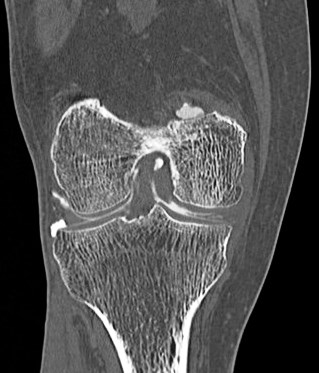

68 yo male with medial knee pain and a pacemaker.

Figure 2 for case Medial meniscus tear ( RID2772 )

Figure 2

Oblique tear of the medial meniscus shown on a CT arthrogram.

Medial meniscus tear ( RID2772 )